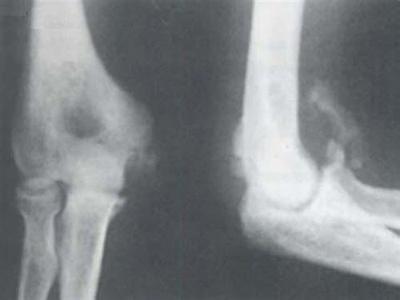

2.其他辅助检查 在3~6周后,X线摄片可见到骨化影。开始呈云雾状环状钙化,以后逐渐轮廓清楚,中央透亮。成熟后外周骨化明显致密,其内为骨小梁。

辅助检查:X线片见骨化影,开始呈云雾状环形钙化,以后逐渐轮廓清楚,中央透亮。数月后骨化,关节功能受限,应考虑本病。